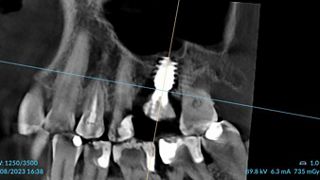

3a. 3b. 3c. 3D volumetric diagnosis and planning of implant therapy.

3a

3b

3c

4. Radiograph exhibiting a suitable septum for immediate implant placement.

4